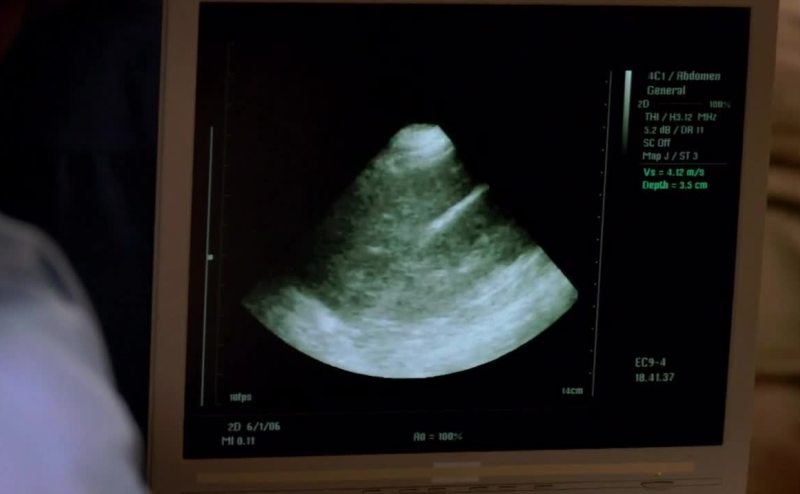

Possible shrapnel wound to the belly,

lower right quadrant to left lower flank.

FAST shows intra-abdominal fluid.

- He's bleeding from somewhere. - All right, let's get him in.